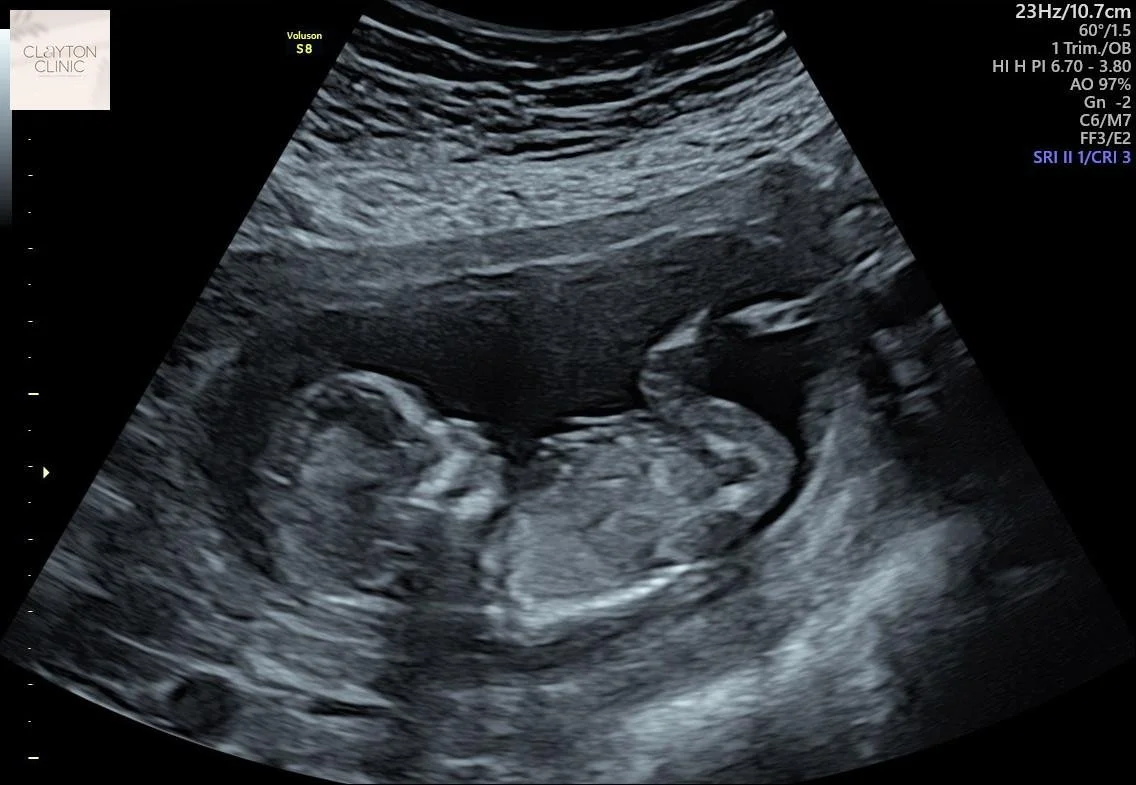

Beta hCG is a protein produced during pregnancy that confirms fetal development and tracks its growth. This test ensures the presence of a pregnancy and allows for regular monitoring to ensure a healthy pregnancy.